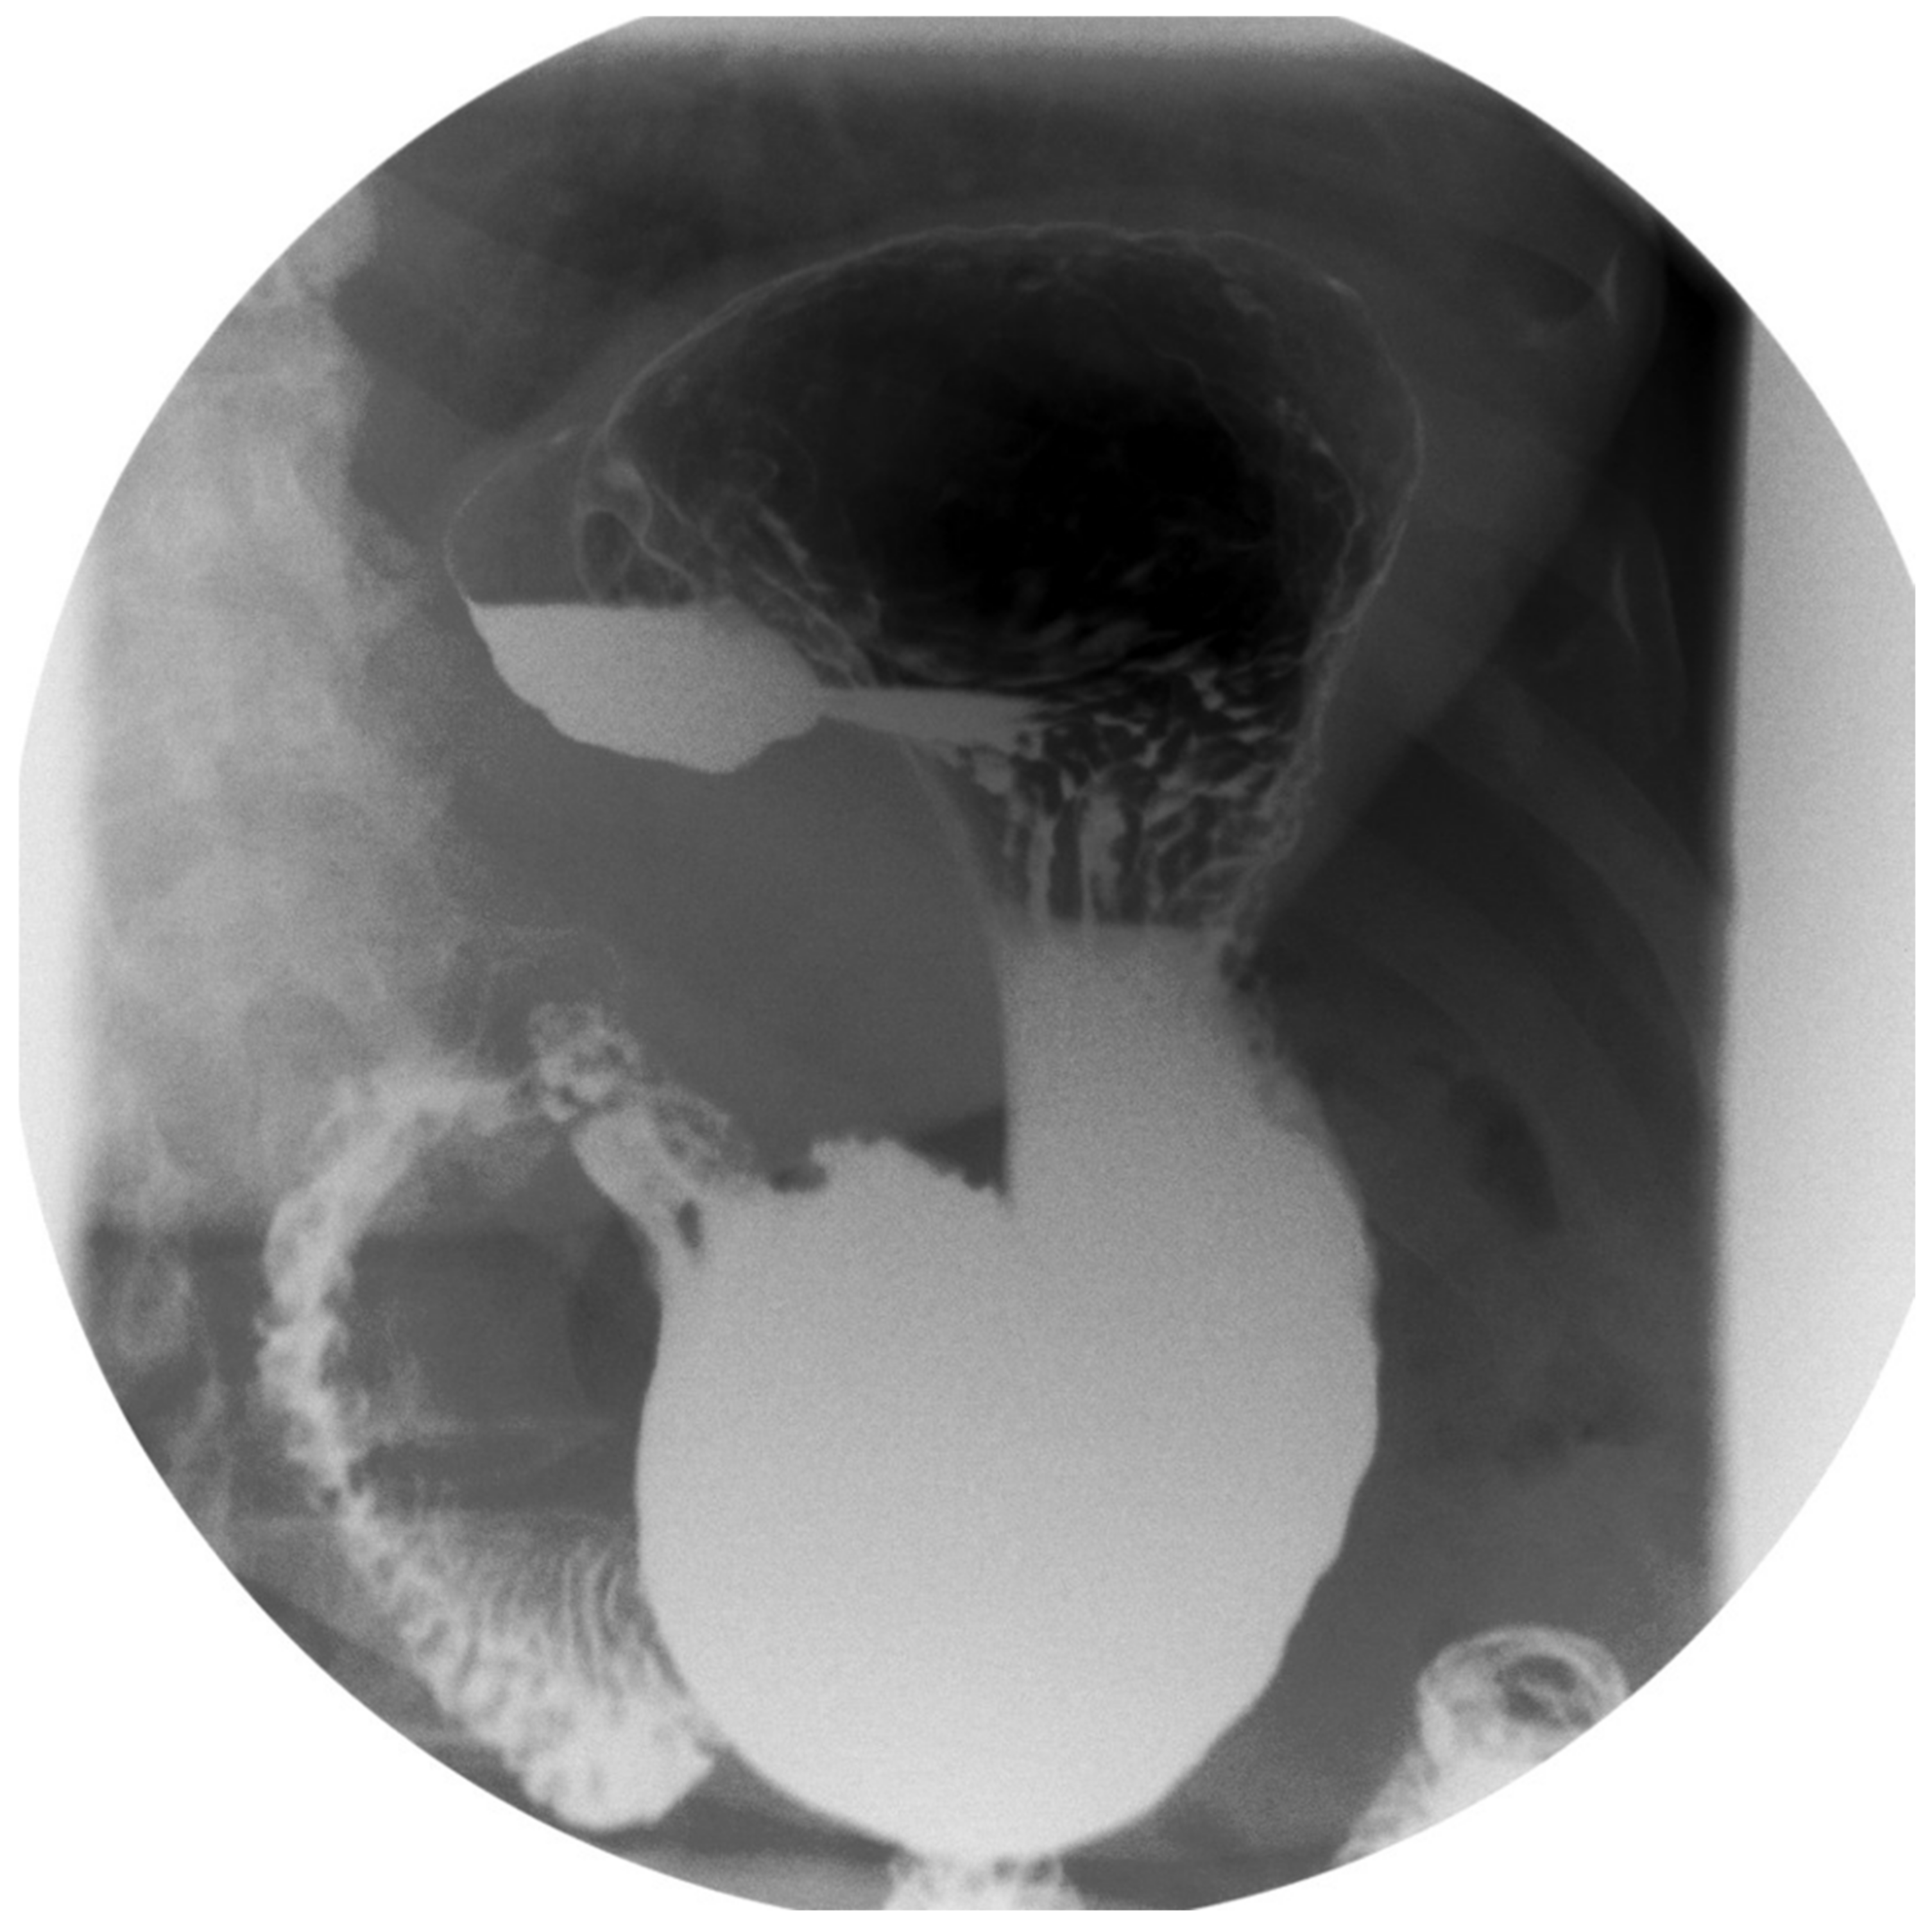

1.1. Gastric Diverticula and Sleeve Gastrectomy

1.2. Technical Considerations